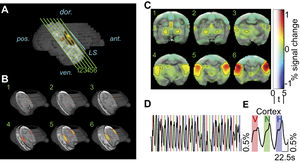

- 3.22 High-field Functional Magnetic Resonance Imaging of Vocalization Processing in Marmosets